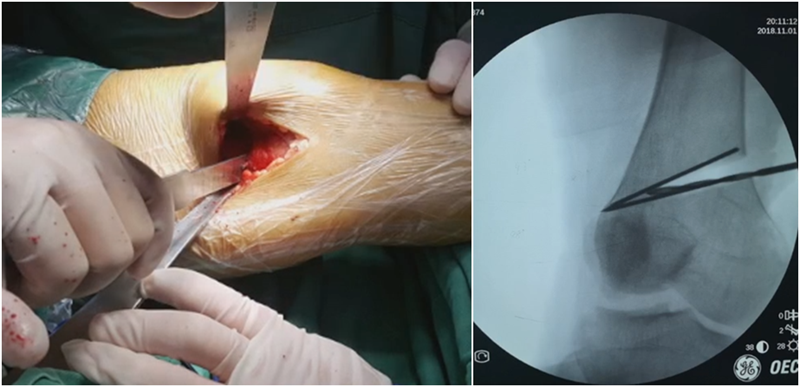

合页点定位有两种方法,一种为定位在股骨外后髁上缘2mm位置,通常将此区域叫做“鹰嘴区”,以此为解剖标记法来定位合页点。

另一种通过导针从截骨入点向股骨外后髁后缘打出一条切线,此切线与外侧骨皮质的交点,也可作为合页点,这种方法称为导针法。这两种方法在手术之中是可以互为验证的。

4、截骨

合页点和截骨线已确定好,按照术前计划打入导针,测量截骨深度。

水平截骨时,同样放肢体中立位,后侧放一把骨撬保护后方重要结构。